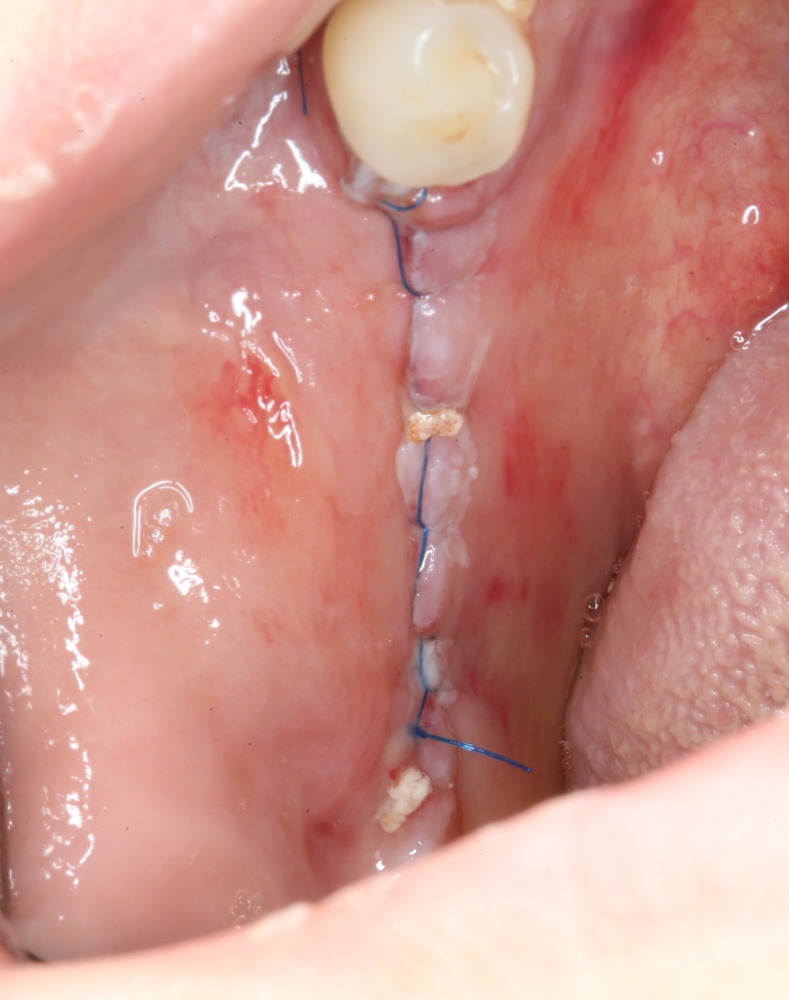

9. Наложение швов.

Я ни разу не испытывал каких-то проблем с ушиванием операционной раны. Как правило, её края сходятся достаточно легко без дополнительной периостотомии. Для наложения швов мы используем монофиламентные нерезорбируемые нити диаметром 5-0 (Resolone, Prolene, Полипропилен и др.).

Обычно, через день после операции рана выглядит вот таким образом:

Швы можно снять на 10-14 день.